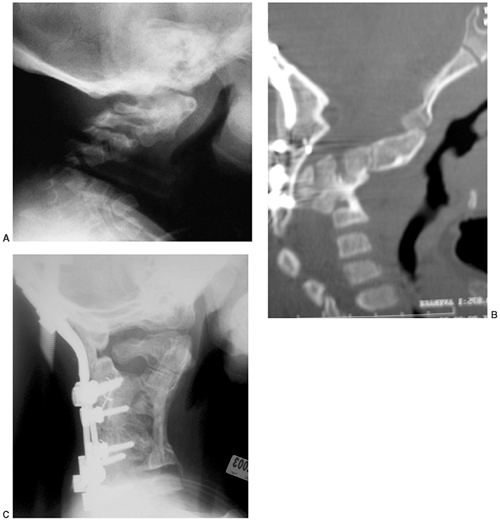

Cervical kyphosis is seen in one third to one half of patients (8,91);

this disorder may be present in infancy, and its course is variable.

Spontaneous resolution has been reported in a number of patients, even

in those with curves of up to 80 degrees (92,93) (Fig. 8.16 A, B). However, other cases progress, and there are several reports of quadriparesis resulting from this deformity (8,94). Scoliosis develops in at least one third of patients (91),

Figure 8.16 Cervical kyphosis in a 1-year-old child (A)

with diastrophic dysplasia is pronounced, with marked deformity of C4. The findings of neurologic examination are normal. Four years later, the condition is markedly improved without any intervention (B), and 7 years later the vertebral bodies have been restored to nearly normal shape, although the canal remains narrow (C). |